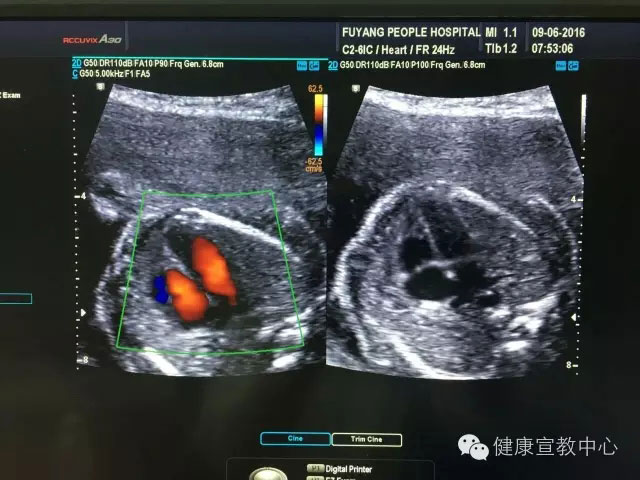

胎兒專項(xiàng)系統(tǒng)檢查是建立在胎兒中孕系統(tǒng)超聲檢查的基礎(chǔ)上對所篩查的器官、作更系統(tǒng)化精細(xì)化檢查。從2015年,開展胎兒專項(xiàng)系統(tǒng)篩查(胎兒心臟、胎兒中樞神經(jīng)系統(tǒng)、顱腦微小畸形、脊柱等)以來,共計(jì)完成400余例。目前,該項(xiàng)技術(shù)處于省內(nèi)領(lǐng)先水平,部分省級醫(yī)院還尚未開展。

(胎兒超聲心動圖)